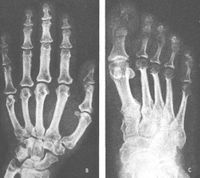

1.X線片檢查可見肢端肥大症患者的蝶鞍擴大,占位病變致鞍周受壓與侵蝕,鞍背骨、鞍底骨或其交界處骨質經常有骨質吸收。有作者觀察937例正常人鞍前後徑為7~16mm(平均11.7mm),深徑7~14mm(平均9.5mm),肢端肥大症患者的蝶鞍可大於25mm,故常伴有頭痛及視力減退等壓迫症狀。骨骼系統X線檢查還可發現顱骨、顴骨、枕骨隆突增大加厚,下頜骨增大前突,牙列稀疏,指骨及足趾骨末節增大。加之軟組織肥厚,手足增大變寬,脊柱骨、軟組織增生,骨膜鈣化形成骨質增生,但也常發生骨質疏鬆及關節病變。

肢端肥大症 (1)手相:手指遠端指骨端增寬,呈叢狀圓形;近端指骨骨幹因新骨形成而變粗。

(3)足側位相:足跟脂肪墊增厚。當男女脂肪墊,分別大於23mm及21.5mm時,應高度懷疑本病。如分別大於25mm和23mm則可診斷本病。